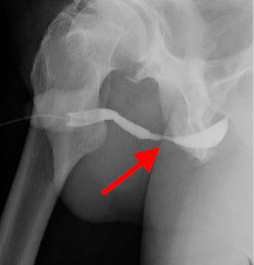

Scar tissue causing obstruction

A urethral stricture is scar tissue causing obstruction to urinary flow. It can be caused by having had a urethral catheter, urethral surgery, or pelvic trauma (such as a pelvic fracture), but often there is no obvious cause.